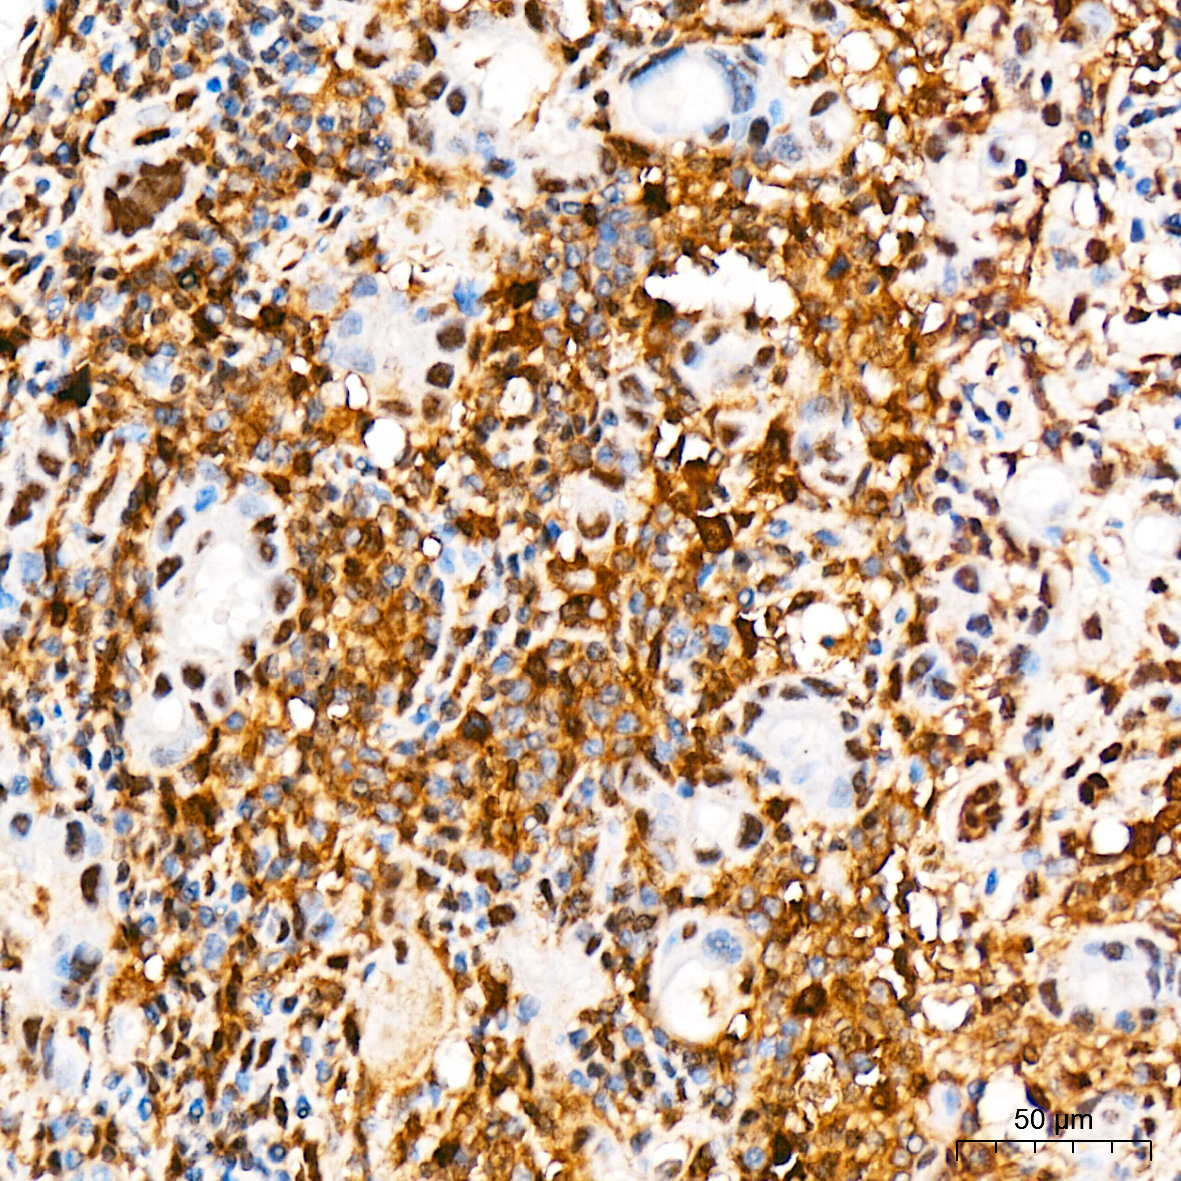

| Immunohistochemistry analysis of paraffin-embedded Human breast tissue using [KO Validated] STAT3 Rabbit mAb (A19566) at a dilution of 1:200 (40x lens). High pressure antigen retrieval was performed with 0.01 M citrate buffer (pH 6.0) prior to IHC staining. |

| Immunohistochemistry analysis of paraffin-embedded Human thyroid cancer tissue using [KO Validated] STAT3 Rabbit mAb (A19566) at a dilution of 1:200 (40x lens). High pressure antigen retrieval was performed with 0.01 M citrate buffer (pH 6.0) prior to IHC staining. |

| Immunohistochemistry analysis of paraffin-embedded Human brain tissue using [KO Validated] STAT3 Rabbit mAb (A19566) at a dilution of 1:200 (40x lens). High pressure antigen retrieval was performed with 0.01 M citrate buffer (pH 6.0) prior to IHC staining. |